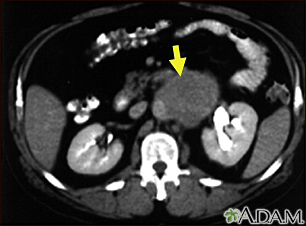

Lymph node metastases, CT scanBackLymph node metastases, CT scanA CT scan of the middle abdomen showing a large tumor mass due to metastasis (spreading cancer) in abdominal lymph nodes. E-mail FormEmail ResultsName:Email address:Recipients Name:Recipients address:Message: